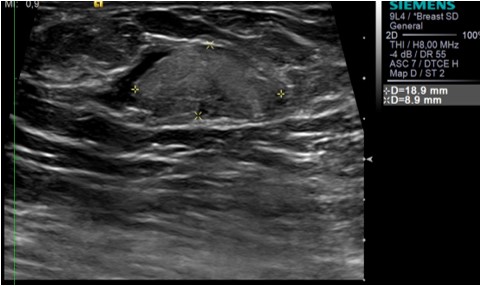

BI-RADS 2 Benign Pseudohamartoma appearance of a Chronic Galactocele within the accessory breast tissue

Galactocele is a milk-filled retention cyst caused by the obstruction of the lactiferous duct. It is the most common benign breast mass in women who are or who recently stopped lactating. Clinically, it manifests as one or multiple painless palpable masses On mammography, galactocele can exhibit various imaging features depending on the proportion of fat and protein in the individual's breast milk. When completely radiolucent with a relatively high fat content, it is known as pseudolipoma. A cystic mass with a fat-fluid level is a diagnostic indicator of a galactocele, with the fat content above and the water content remaining at the bottom. Alternatively, when the high viscosity of breast milk does not allow the separation of the fat and water contents, a galactocele can resemble a hamartoma; this condition is known as pseudohamartoma

Mammography Accessory breast tissue in the left axillary region. Fat containing oval mass with circumscribed margins and a thin capsule around it. Additional left axillary tail view done . Ultrasound Oval mass with circumscribed margin,complex solid and cystic with no vascularity on color doppler.